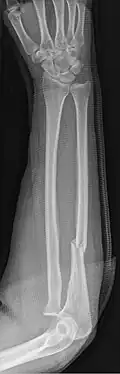

Fractures of the ulna can occur at different levels of the bone: near the wrist, in the middle or near the elbow.[2] The fracture may be confined to the ulna or accompanied with damage to the radius or the wrist or elbow joints.[2]

- Nightstick fracture is a fracture of the middle portion of the ulna without other fractures.[1]

- Monteggia fracture - a fracture of the near to elbow end of the ulna with the dislocation of the head of the radius at the elbow joint.[2]